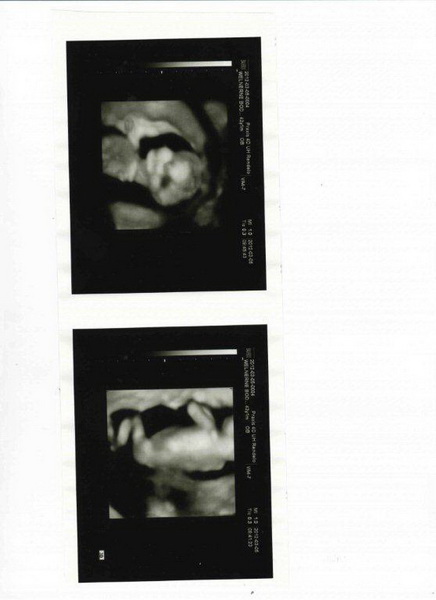

Csináltam képet a dvd-ből a kicsiről. Feltöltöm. Kis turcsi orrú baba. Kép